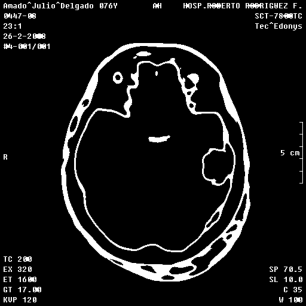

An example of an applications of our proposed strategy to a medical image is shown in Figure 7. In this case, we used different values of and in the . This is a preliminary result. A deeper paper about these results will be published.